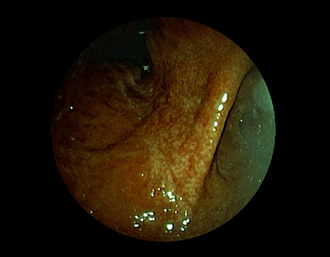

症例4:ヘリコバクター・ピロリ感染胃炎(42才、男性)

萎縮性胃炎

胃角部小弯に、粘膜表面の萎縮・菲薄化を認める。

通常画像